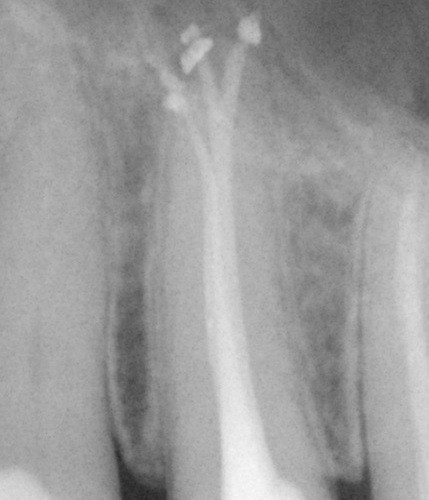

• Náročná anatomie: Praktický a srozumitelný návod, jak zvládnout komplikované kořenové kanálky – zejména typu MB2 a dolní moláry v běžné praxi. Zaměření na přístup, možné komplikace a plnění kořenových kanálků, srovnání ručních technik a strojové endodoncie.

• Opracování MB2 (Biovoxel/trepanovaný horní molár č. 16) za použití nástrojů systémů PTUL a TN.

• Zaplnění k.k..